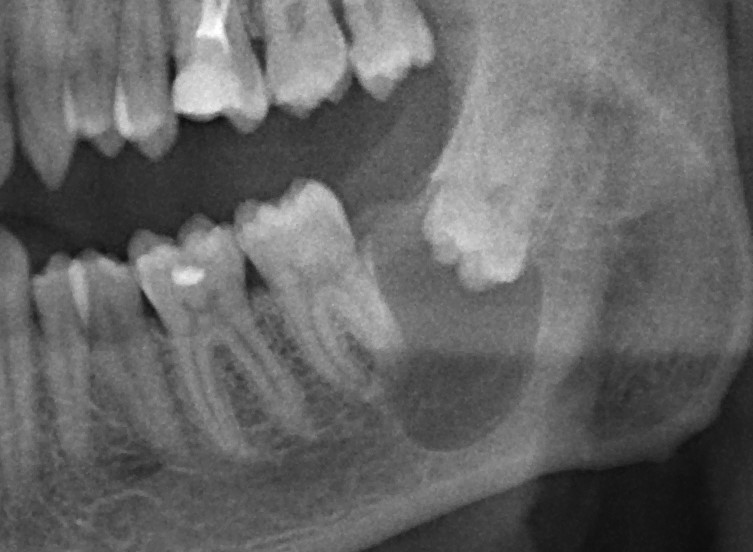

Ключевой семинар по использованию биоматериалов в имплантологии, остеопластических операциях, мукогингивальной хирургии и хирургической пародонтологии. Я спланировал семинар как ответ на главный вопрос: «Почему нам вообще нужны биоматериалы, и можем ли мы без них обойтись?» В ходе семинара подробно рассмотрены основные методики регенерации костной ткани, начиная от пластики крупными аутокостными фрагментами, заканчивая направленной костной регенерацией, с имплантами или без.

Как видно из названия, семинар посвящен самой частой и распространенной хирургической операции в мире — удалению зубов. Это новое мероприятие в моем графике, мы проводим его совместно с IDA (International Dentistry Association). В ходе семинара будут рассмотрены различные методики удаления зубов, в том числе удаление ретинированных зубов мудрости, сверхкомплектных зубов, а также операции, включающие в себя эту процедуру: немедленная имплантация и превентивная аугментация лунок.

Это мой самый любимый и тщательно подготовленный проект — семинар по немедленной имплантации. Он уже дважды был в Москве, и однажды — в Нижнем Новгороде. На этот раз, мы проводим его совместно с компанией APEX в Санкт-Петербурге, и посвящен он будет… догадайтесь с трех раз?))) Через фокус немедленной имплантации будут рассмотрены различные имплантационные системы, операции остеопластики, синуслифтинга, удаления зубов и превентивной аугментации лунок.